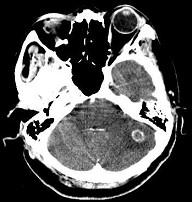

问题 男,62岁,既往有右肺腺癌史,现出现头痛、头晕、恶心、视物模糊,CT检查如图,最可能的诊断是()

选项 A.脑梗死 B.胶质瘤 C.脑膜瘤 D.畸胎瘤 E.脑转移瘤

答案 E